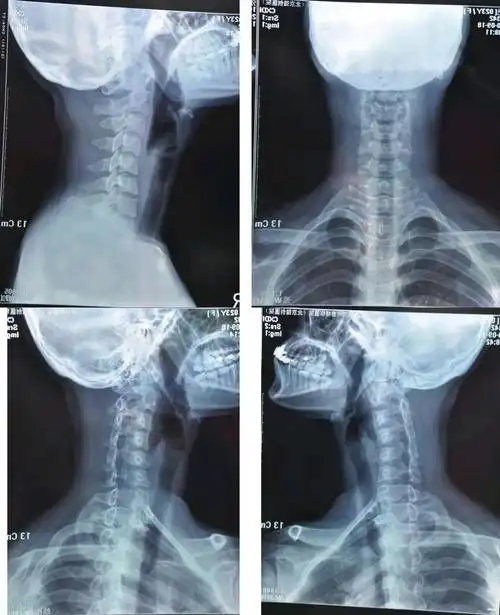

颈椎反弓要手术纠正?看完后,我马上抬起了头!

当颈椎反弓时,容易压迫颈椎周围的神经,引起神经症状和严重的后果.

生理性前凸,低头族的颈椎会逐渐向相反方向弯曲,出现"颈椎反曲""反弓"